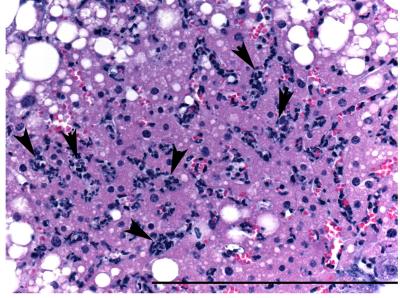

Illness and death caused by viral infections tend to increase with age, indicating that aging impairs immunity, but the underlying mechanisms are unclear. To understand how aging modifies inflammatory response to viral infection, a research team led by Daniel R. Goldstein, M.D., associate professor of internal medicine and cardiology at Yale School of Medicine, infected young (2-4 months), middle-aged (8-10 months), and aged (18-20 months) mice with the herpes virus. This led to a rapid increase in inflammatory mediators, or cytokines, called interleuken 17. When the team examined the blood for inflammatory substances and examined the liver, they saw evidence of damage in only the aged cohort.

When Goldstein and his team inhibited interleuken 17 either before or after infection, the mice in the aged group no longer showed signs of liver damage and no longer died. Goldstein said the study's results demonstrate that aged individuals succumb to viral infection due to exaggerated immune responses rather than declining immunity.